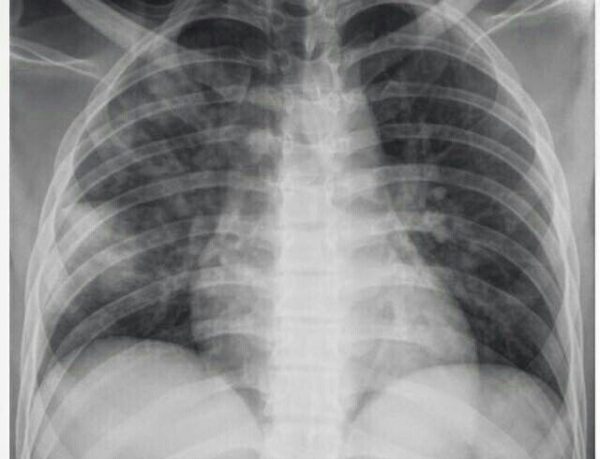

La radiografía de tórax constituye una herramienta fundamental en el abordaje diagnóstico de las enfermedades pulmonares. Se trata de un estudio radiológico de primera línea que permite obtener una visión global de las estructuras intratorácicas, siendo especialmente útil por su accesibilidad, rapidez, bajo costo y capacidad para proporcionar información diagnóstica valiosa en tiempo real. Su utilidad se extiende desde la evaluación inicial en pacientes con síntomas respiratorios inespecíficos hasta el seguimiento de enfermedades pulmonares crónicas o la identificación de complicaciones agudas.

Desde el punto de vista técnico, una radiografía de tórax estándar debe realizarse en posición erguida, durante una inspiración máxima, y con un haz de rayos de alta energía, lo que garantiza una adecuada penetración de las estructuras torácicas. Las proyecciones convencionales incluyen la vista posteroanterior y la lateral, las cuales son complementarias y permiten una mejor delimitación de las lesiones, al reducir la superposición de estructuras. La proyección lateral es particularmente útil para explorar regiones que pueden pasar desapercibidas en la vista frontal, como los lóbulos inferiores, las áreas retrocardíacas o la región paravertebral.

La interpretación sistemática de una radiografía de tórax es crucial para evitar omisiones diagnósticas. El análisis debe iniciar con una revisión técnica que evalúe aspectos como la calidad de la inspiración, el centrado anatómico y la penetración del haz de rayos. Una radiografía óptima permite visualizar las vértebras torácicas a través de la silueta cardíaca y evidencia un número mínimo de espacios intercostales visibles, lo que indica una adecuada expansión pulmonar. La correcta alineación de las apófisis espinosas con respecto a las clavículas es indicativa de una imagen bien centrada, sin rotación.

Superada esta etapa técnica, la lectura clínica se realiza de manera ordenada, iniciando por el esqueleto torácico y las partes blandas, donde pueden evidenciarse fracturas costales, lesiones osteolíticas, masas de partes blandas o signos indirectos de patologías subyacentes. Posteriormente, se exploran el mediastino y la silueta cardíaca, analizando su forma, tamaño y contornos, así como los hilios pulmonares, cuya morfología puede alterarse en presencia de adenopatías o procesos vasculares. Finalmente, se examinan los campos pulmonares en busca de opacidades, hiperclaridades, engrosamientos pleurales, derrames o signos indirectos de colapso o hiperinsuflación.